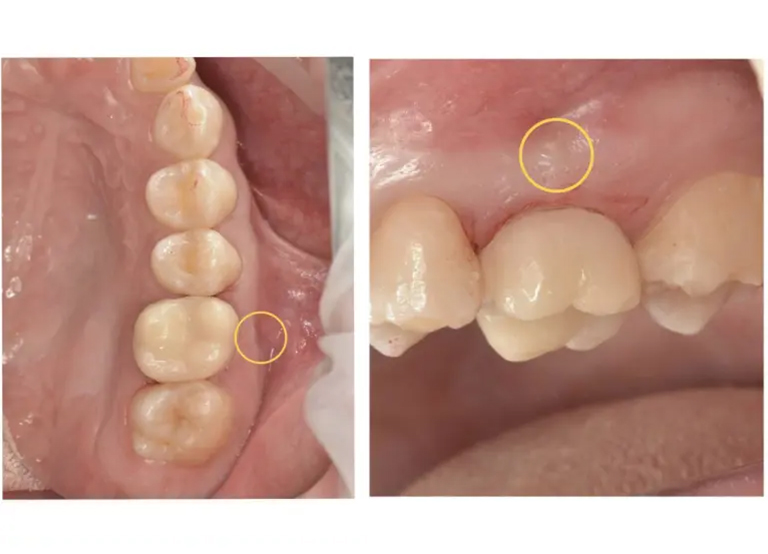

部位は右下の5番目です。

根っこの先の骨が溶けて黒くなっているのが確認できます。

こちらが膿が溜まった後出口として、歯茎の表面に出来物(フィステル)ができた様子です。

この歯は神経が残っている歯でしたが、残念ながら失活(神経が死んでしまうこと)してしまっていました。その為、歯の根っこの中を消毒する処置を行います。 -

根管治療を行った後、骨が回復するまで6ヶ月ほど経過観察を行います。こちらは治療後6ヶ月のレントゲンとCTの写真です。

まだ少し黒い影はあるものの、薄く骨のようなものがモヤっとできており、溶けていた根っこの先の骨が大きく回復傾向にあるのがわかります。

大きく腫れてしまっていた歯茎も根っこの膿の消失とともに治癒しました。